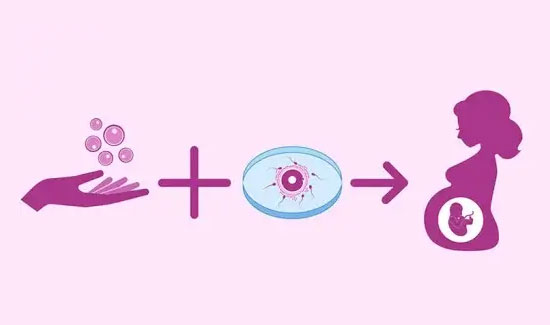

At the best IVF Hospital in Nagarbhavi, Bangalore, The IVF Procedure is usually done under the watchful eyes and directions of a seasoned experts. This procedure involves the following steps.

STEP 1

Stimulating the ovaries

STEP 2

Egg Retrieval

STEP 3

Fertilization of eggs

STEP 4

Embryo Culture

STEP 5

Embryo Transfer